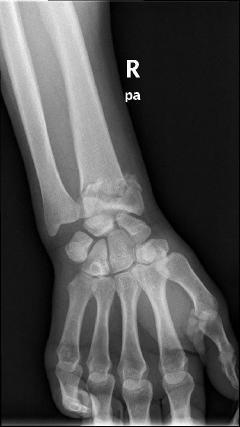

Κατάγματα κάτω πέρατος κερκίδος – κατάγματα Colle’s

Είναι τα συχνότερα κατάγματα στον σκελετό και συμβαίνουν συνήθως σε γυναίκες μετά την εμμηνόπαυση, όταν πέφτουν στο έδαφος και προσπαθούν με συγκρατηθούν βάζοντας την παλάμη. Τα πιο δύσκολα να αντιμετωπιστούν είναι εκείνα που επεκτείνονται μέχρι την αρθρική επιφάνεια.

Περίπτωση 2ου ασθενούς